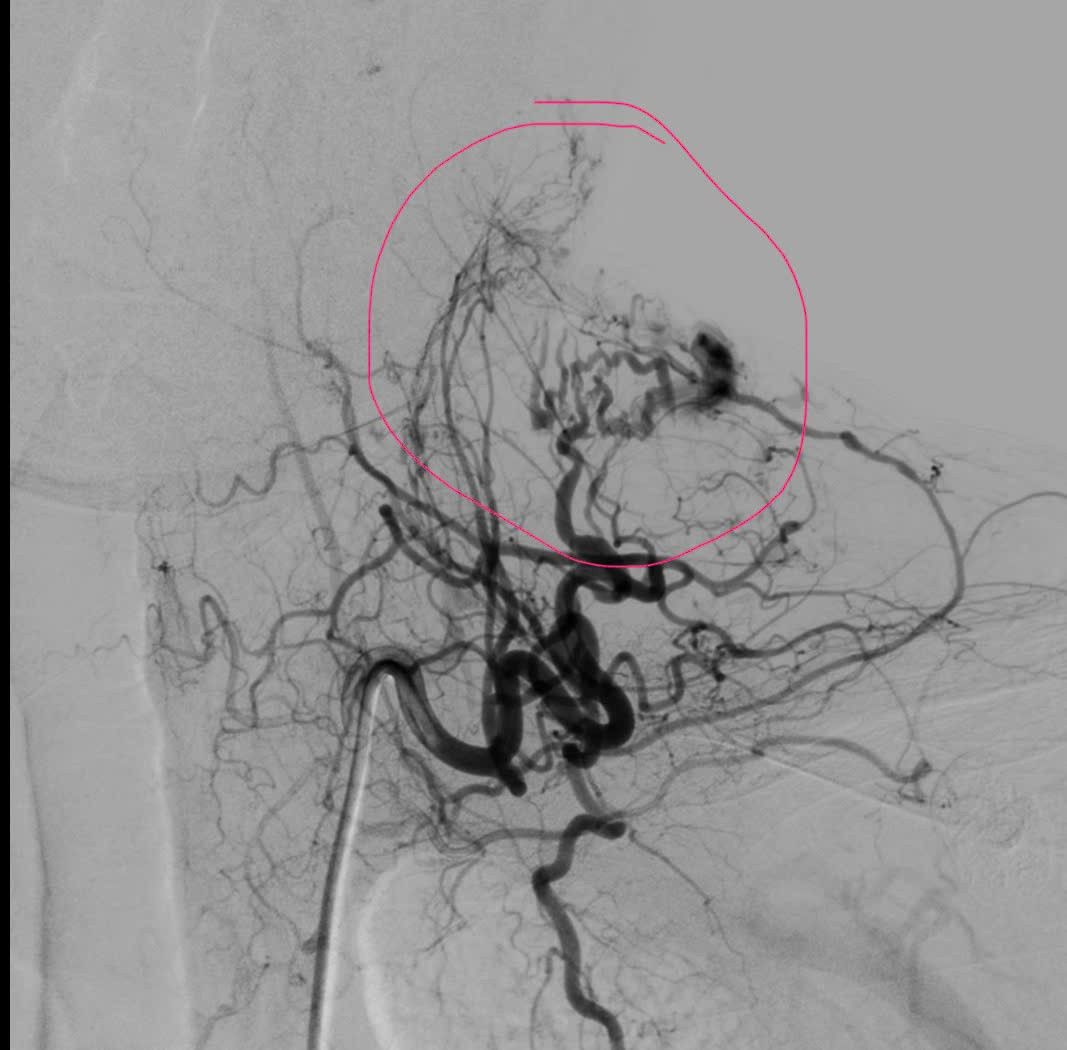

Qua thăm khám lâm sàng kết hợp chụp MSCT, các bác sĩ ghi nhận ổ dị dạng động – tĩnh mạch (AVM) dạng nidus lan tỏa nằm ở phần mềm dưới da vùng cổ. Trước tính chất phức tạp của tổn thương, người bệnh nhanh chóng được hội chẩn đa chuyên khoa, thống nhất chỉ định chụp mạch số hóa xóa nền (DSA) và can thiệp nút mạch cầm máu.

bam-nho-2.jpg

Vỡ ổ dị dạng động tĩnh mạch - Ảnh BVCC

Kết quả chụp DSA cho thấy ổ dị dạng được nuôi dưỡng bởi nhiều cuống mạch xuất phát từ thân giáp cổ, kèm theo hệ tĩnh mạch dẫn lưu nông giãn lớn lan vùng cổ, vai, lưng, làm tăng nguy cơ chảy máu tái phát nếu không xử trí triệt để.

Dưới hướng dẫn hình ảnh chính xác, ê-kíp đã tiến hành nút tắc chọn lọc từng cuống mạch nuôi bằng keo sinh học, giúp giảm rõ rệt dòng chảy trong ổ dị dạng. Sau can thiệp, người bệnh được khâu vết rách da, băng ép tại chỗ, tình trạng chảy máu cơ bản được kiểm soát hoàn toàn. Toàn trạng ổn định, người bệnh được chuyển về Hồi sức cấp cứu để tiếp tục theo dõi sát.